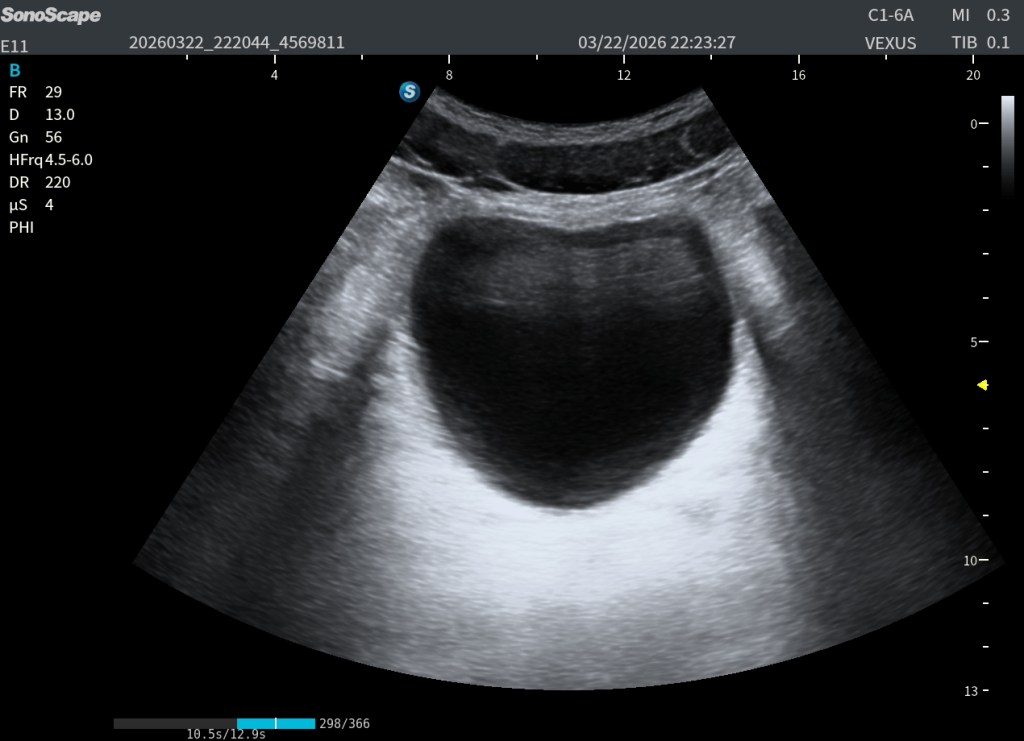

Caso práctico: la vejiga y el falso problema del refuerzo posterior

Un ejemplo muy claro, muy habitual y muy didáctico es la vejiga urinaria.

La vejiga, cuando está bien distendida, es una estructura anecoica con un alto contenido líquido. Esto genera un fenómeno clásico: un refuerzo posterior muy intenso, extremadamente brillante:

Este refuerzo tiene varias consecuencias:

- Aparece una zona hiperecogénica posterior muy llamativa

- Se generan ecos dentro de la vejiga que no son reales

- Se pierde contraste

- Y, lo más importante, dificulta la visualización de estructuras posteriores

Un ejemplo claro son las vesículas seminales, que en muchas ocasiones quedan ocultas o mal definidas por ese exceso de brillo.